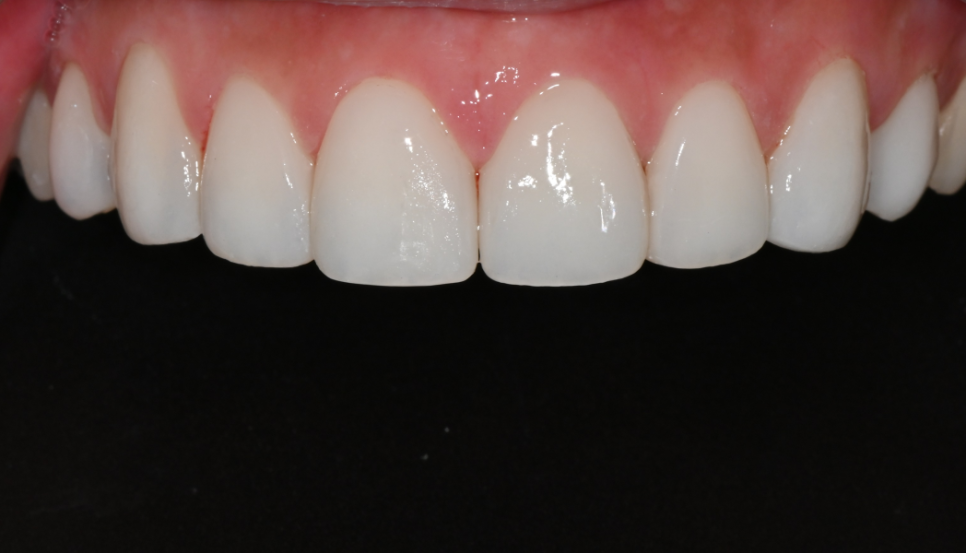

Clean Jamsil laminate veneers without a translucent layer

The final laminate veneers were made in a tone with very little translucent layering, as requested by the patient.

To avoid making the veneers look obviously like veneers, we brought out a matte sheen similar to natural teeth and adjusted the line from the front teeth to the canines so it matched naturally with lip movement.

Laminate veneers with a plastic-like glossy material tend to feel more uniformly monochromatic than matte, and this is usually why people say, “Laminate veneers look unnatural.”

Ovezero laminate veneers express a matte texture so that the teeth do not stand out even when catching the light, allowing for a neat smile line from any angle.

After placement, the patient looked in the mirror and was very satisfied, saying,

“It feels like my impression has been neatly refined,”

“It's bright, but not excessive at all.”